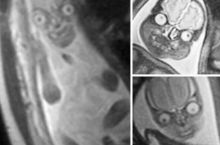

The reason why pregnant people get ultrasounds and not MRIs, is that in an MRI, this is what a fetus looks like